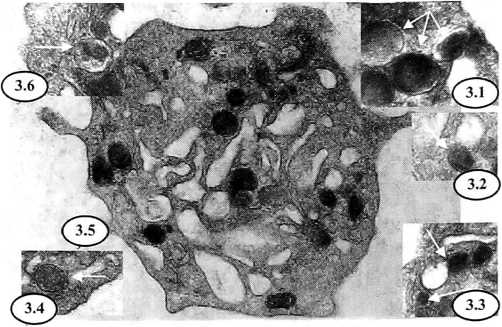

Рис. 3. Экваториальный срез циркулирующего тромбоцита женщины при беременности, осложненной ОПГ-гестозом легкой степени:

3.1 — альфа-гранулы возле ПВС и контакт их мембран (>50000);

3.2 — альфа-гранула с матриксом сниженной электронной плотности, контактирующая с ПВС (X35000);

3.3 — экзоцитоз содержимого альфа-гранулы в ПВС и непосредственный контакт мембран плотного тельца с ПВС (X50000);

3.4 и 3.5 — цитоплазматические мембранные включения (варианты) возле ПВС (×65000 и ×50000);

3.6 — аутофагосома (×50000)

При этом увеличение в плазме крови активности фактора 4 тромбоцитов (см. рис. 1) который непосредственно локализуется в тромбоцитарных альфа-гранулах [5], свидетельствует о степени развития в циркулирующих тромбоцитах реакции высвобождения [27]. Именно интенсивность морфологических проявлений тромбоцитарной реакции высвобождения обусловливает значительное нарастание числа гипогранулярных (см. рис. 3 и 4) и даже агранулярных форм тромбоцитов в крови при беременности осложненной ОПГ-гестозом (см. рис. 1). На фоне установленной реакции экстратромбоцитарного выделения содержимого цитоплазматических альфа-гранул в циркулирующих тромбоцитах женщин при физиологической и осложненной ОПГ-гестозом беременности нами выявлены и другие изменения, происходящие в зоне тромбоцитарных органелл. Так, при легкой форме клинических проявлений ОПГ-гестоза в ультратонких экваториальных срезах циркулирующих тромбоцитов визуализируется увеличение количества плотных телец и цитоплазматических мембранных включений, а при среднетяжелой степени ОПГ-гестоза количество этих тромбоцитарных органелл резко уменьшено (см. рис. 1), вплоть до их полного отсутствия (см. рис. 4). Плотные тельца в тромбоцитах человека рассматриваются, как определенная группа цитоплазматических гранул, более мелких, ограниченных трехслойной мембраной, имеющих светлый матрикс с электронноплотной сердцевиной в центре [34]. Наряду с имеющимися данными, указывающими на возможность формирования этих органелл из плотной тубулярной системы тромбоцитов [20], характерные структурные, энзиматические и функциональные особенности плотных телец свидетельствуют о происхождении их из альфа-гранул [3, 34]. Последние также непосредственно участвуют в образовании цитоплазматических мембранных включений, представляющих собой округлые спиралевидные плотные мембранные 2—3 витка и которые по ряду специфических признаков не могут быть отнесенными к миелоподобным структурам [3]. При беременности, осложненной ОПГ-гестозом, на тромбоцитарных электроннограммах определяется значительное уменьшение содержания в цитоплазме гранул гликогена (см. рис. 1, 3, 4) или бета-гранул величиной до 25 нм, обеспечивающих функциональный энергетический ресурс тромбоцитов [10]. При этом появление в цитоплазме циркулирующих тромбоцитов аутофагосом (рис. 3) указывает на развитие деградационных процессов [3]. Вероятно, такие внутритромбоцитарные изменения не позволяют морфологически идентифицировать покрытые или окаймленные пузырьки [3] и митохондрии в цитоплазме большинства циркулирующих тромбоцитов при выраженных клинических симптомах ОПГ-гестоза. В данном случае реактивные сдвиги в зоне органелл визуализируются на фоне значительного реформирования обеих внутритромбоцитарных мембранных систем.

Однако анализ известных данных о морфологических изменениях тромбоцитов при их активации [3, 5, 17, 27, 29, 34], факты о наличии в тромбоцитах функционально полноценного лизосомального аппарата [3] и Результаты собственных ультраструктурных исследований указывают на возможность существования ряда особенностей при проявлении тромбоцитарной реакции высвобождения. По нашему мнению, целесообразно дополнить ранее предложенные схемы строения интактных тромбоцитов [19, 35] установленными вариантами экзоцитоза при развитии тромбоцитарной реакции высвобождения (см. рис. 5). А именно, при беременности, осложненной ОПГ-гестозом, альфа-гранулы смещаясь в цитоплазме тромбоцитов, подходят вплотную к структурам комплекса ПВС и после контакта их мембран происходит развитие экзоцитарной реакции (см. рис. 5) с выделением содержимого альфа- гранул в тромбоцитарную дренажную систему (см. рис. 3 и 4).